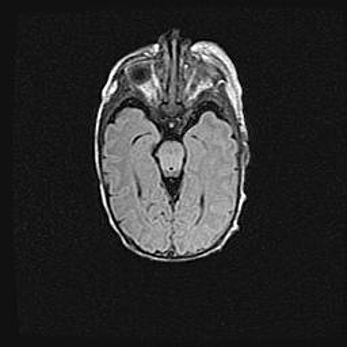

Сообщающаяся гидроцефалия. Кистозная энцефаломаляция головного мозга.

Возраст: 3 месяца 4 дня

Вес: 3100 г

Пол: женский

Окружность головы: 34 см

Срок гестации: 31 неделя

Кистозная энцефаломаляция головного мозга - одна из форм поражения головного мозга в детском возрасте. Характеризуется возникновением множественных и распространённых кист в коре, белом веществе и подкорковых образованиях головного мозга у плодов, новорождённых и детей раннего возраста. Развитие кистозной энцефаломаляции связано с внутриутробной асфиксией и гипотонией, родовой травмой, тромбозом синусов, пороками развития сосудов, инфекциями, сепсисом и другими причинами. Наиболее значимые инфекционные агенты: вирусы простого герпеса, цитомегалии, краснухи, токсоплазмы, энтеробактерии, золотистый стафилококк и другие.